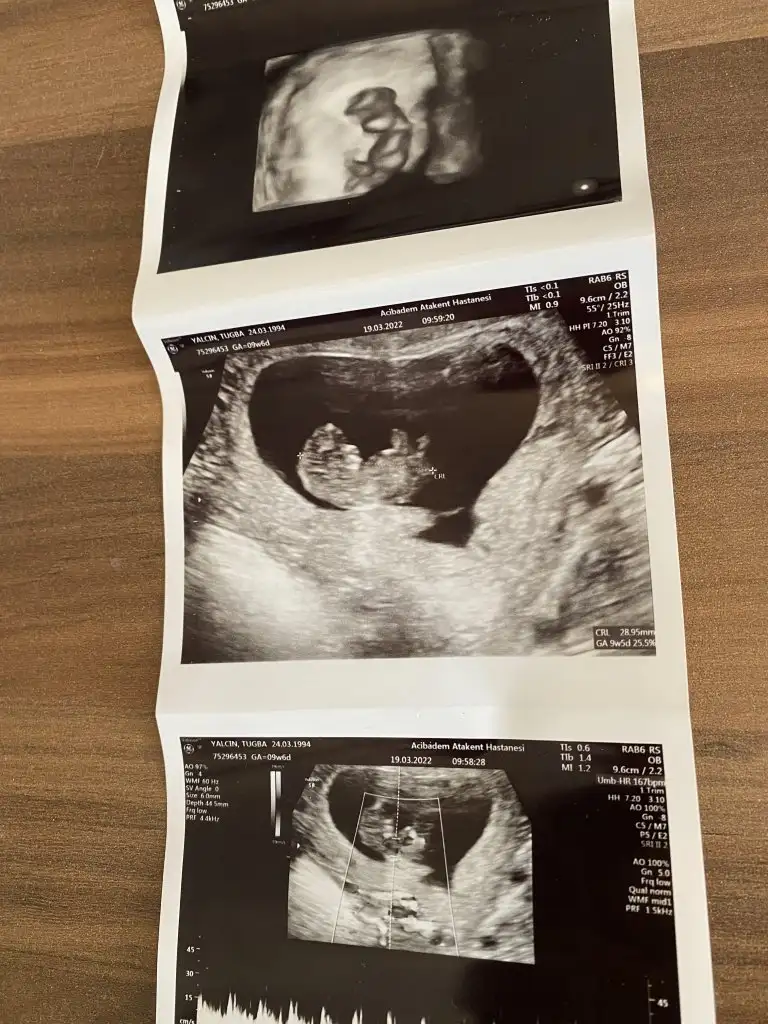

Kız canımHanımlar bizim cinsiyetimiz nedir acaba tahmin edebilir misiniz 12 haftalik

Kız canım